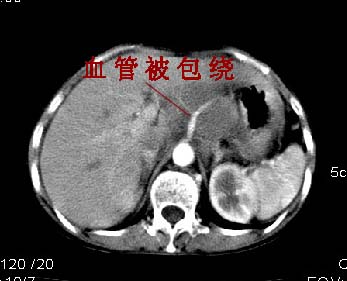

腹膜后淋巴瘤融合成团并包绕周围血管

胰腺受压前移,胰管扩张,应为腹膜后占位,病灶密度不均,有低密度坏死区,强化扫描强化不明显腹腔干动脉受侵,考虑腹膜后恶性占位

从发病部位(腹主动脉周围)及增强方式(均匀轻度强化、少量坏死)和病变形态(较大、多结节形)符合腹膜后淋巴瘤,建议颈部病变活检。

肝胃之间、肝十二指肠韧带,胰头后、腹主a周围,融合而成团块状影,包绕血管[腹腔干、肠系膜上动脉,腹主动脉],胰腺前移后缘分界欠清,与肝胃分界清,肿块未见明显强化,肝右叶后段小囊肿。

主动脉-胰腺间隙可见巨大分叶状软组织肿块影,包绕腹主动脉、腹腔干及其分支、腔静脉等大血管,增强呈无明显强化,临近脏器明显受压移位,增强示有分界。肝右叶可见局限性低密影,边缘清楚。

增强所见,腹腔动脉,肠系膜上动静脉被肿块包绕,结合平扫的条状低密度区恰好位于血管周围,较大的

肿块强化不明显(遗憾的是没有标上ct值)但胃壁强化的十分明显。